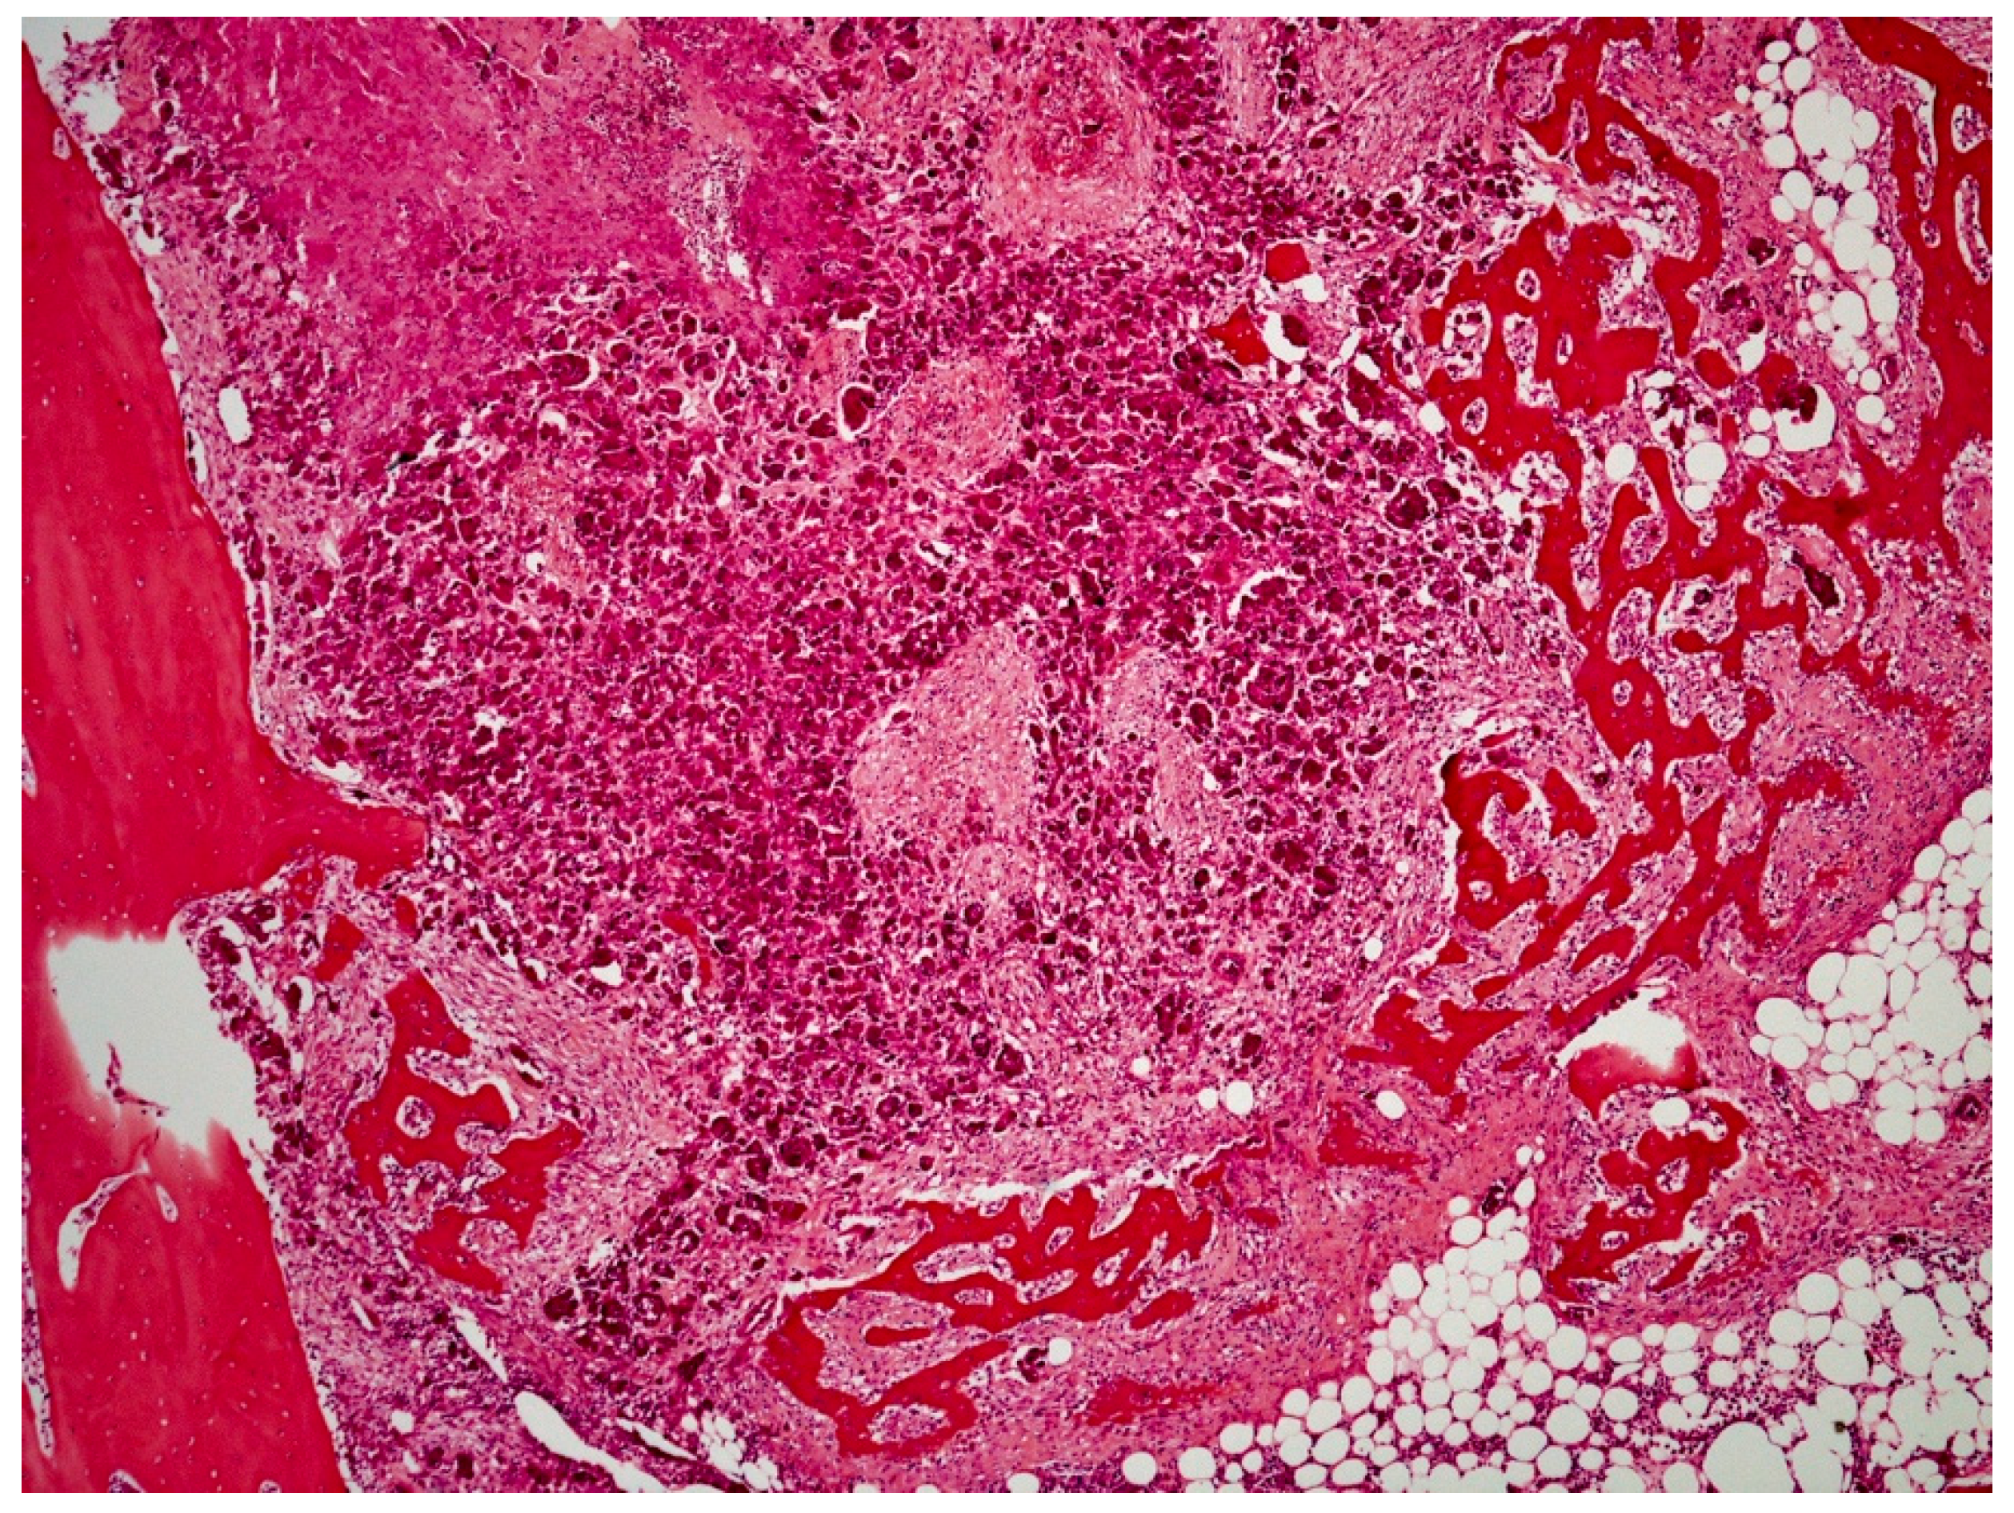

On histological examination (HES stain ×40) (Figure 4), the prostate was invaded and replaced by a poorly defined infiltrative unencapsulated and densely cellular tumor. Tumoral population was arranged in multiple lobules of duct-like structures, lined by unique or multiple layers of pleomorphic neoplastic cells, or occasionally in small clusters of neoplastic cells separated by a plentiful stroma response. Metastatic emboli were numerous. Multiple pulmonary emboli and focal metastatic infiltration with carcinomatous cells (HES stain ×100) (Figure 5) confirmed the severe lymphatic and parenchymatous pulmonary tumor extension, which probably caused the hypertrophic osteopathy. A decalcified longitudinal femur section (HES stain ×40) (Figure 6), showed, from right to left, the cortex, perpendicular bony periosteal trabecular proliferation and an exuberant periosteal reaction characteristic of hypertrophic osteopathy lesions. In addition, several concomitant foci of carcinomatous cells were observed in the medullary cavities of the preexisting bone and in the periosteal proliferation (HES stain ×40) (Figure 7). These observations confirmed the diagnosis of prostatic adenocarcinoma with lymph node, pulmonary, liver and bone metastases, associated with hypertrophic osteopathy.

Figure 4. Prostate invaded by a poorly defined unencapsulated tumor, which is densely cellular and infiltrative (HES stain ×40).